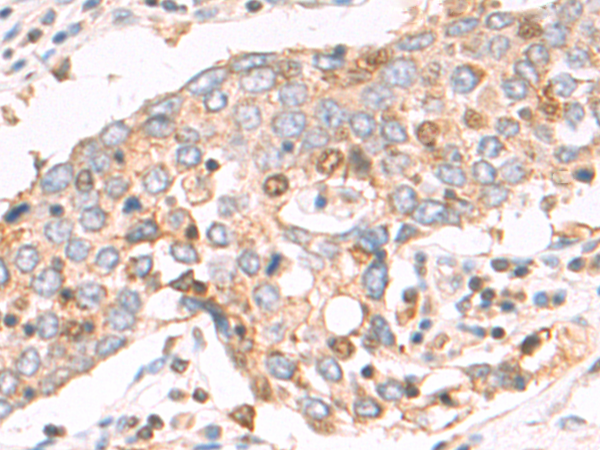

分类: 科研抗体货号: P04969别名: IMB1; IPO1; IPOB; Impnb; NTF97应用: IHC反应种属: Human, Mouse, Rat